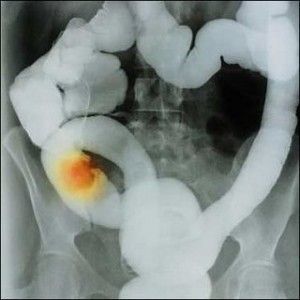

El cáncer colorrectal es responsable de cuatro de cada diez muertes que se producen en España, de ahí la importancia de que los pacientes que sufren esta enfermedad se sometan a las pruebas para la determinación del gen KRAS, con el fin de saber si podrían optar a un tratamiento personalizado más efectivo.

Las mutaciones de este gen están presentes en el 30 al 45% de los casos de este tipo de cáncer, según datos de la Sociedad Americana de Oncología Clínica, de ahí que su recomendación sea analizar el estado mutacional del gen KRAS en todos los pacientes con cáncer colorrectal metastásico, que sean candidatos a recibir un tratamiento basado en anticuerpos anti-EGFR, ya que es un factor predicitivo de la respuesta al tratamiento. Así los pacientes con tumores KRAS nativo presentan una mejor tasa de respuesta y una mayor supervivencia.